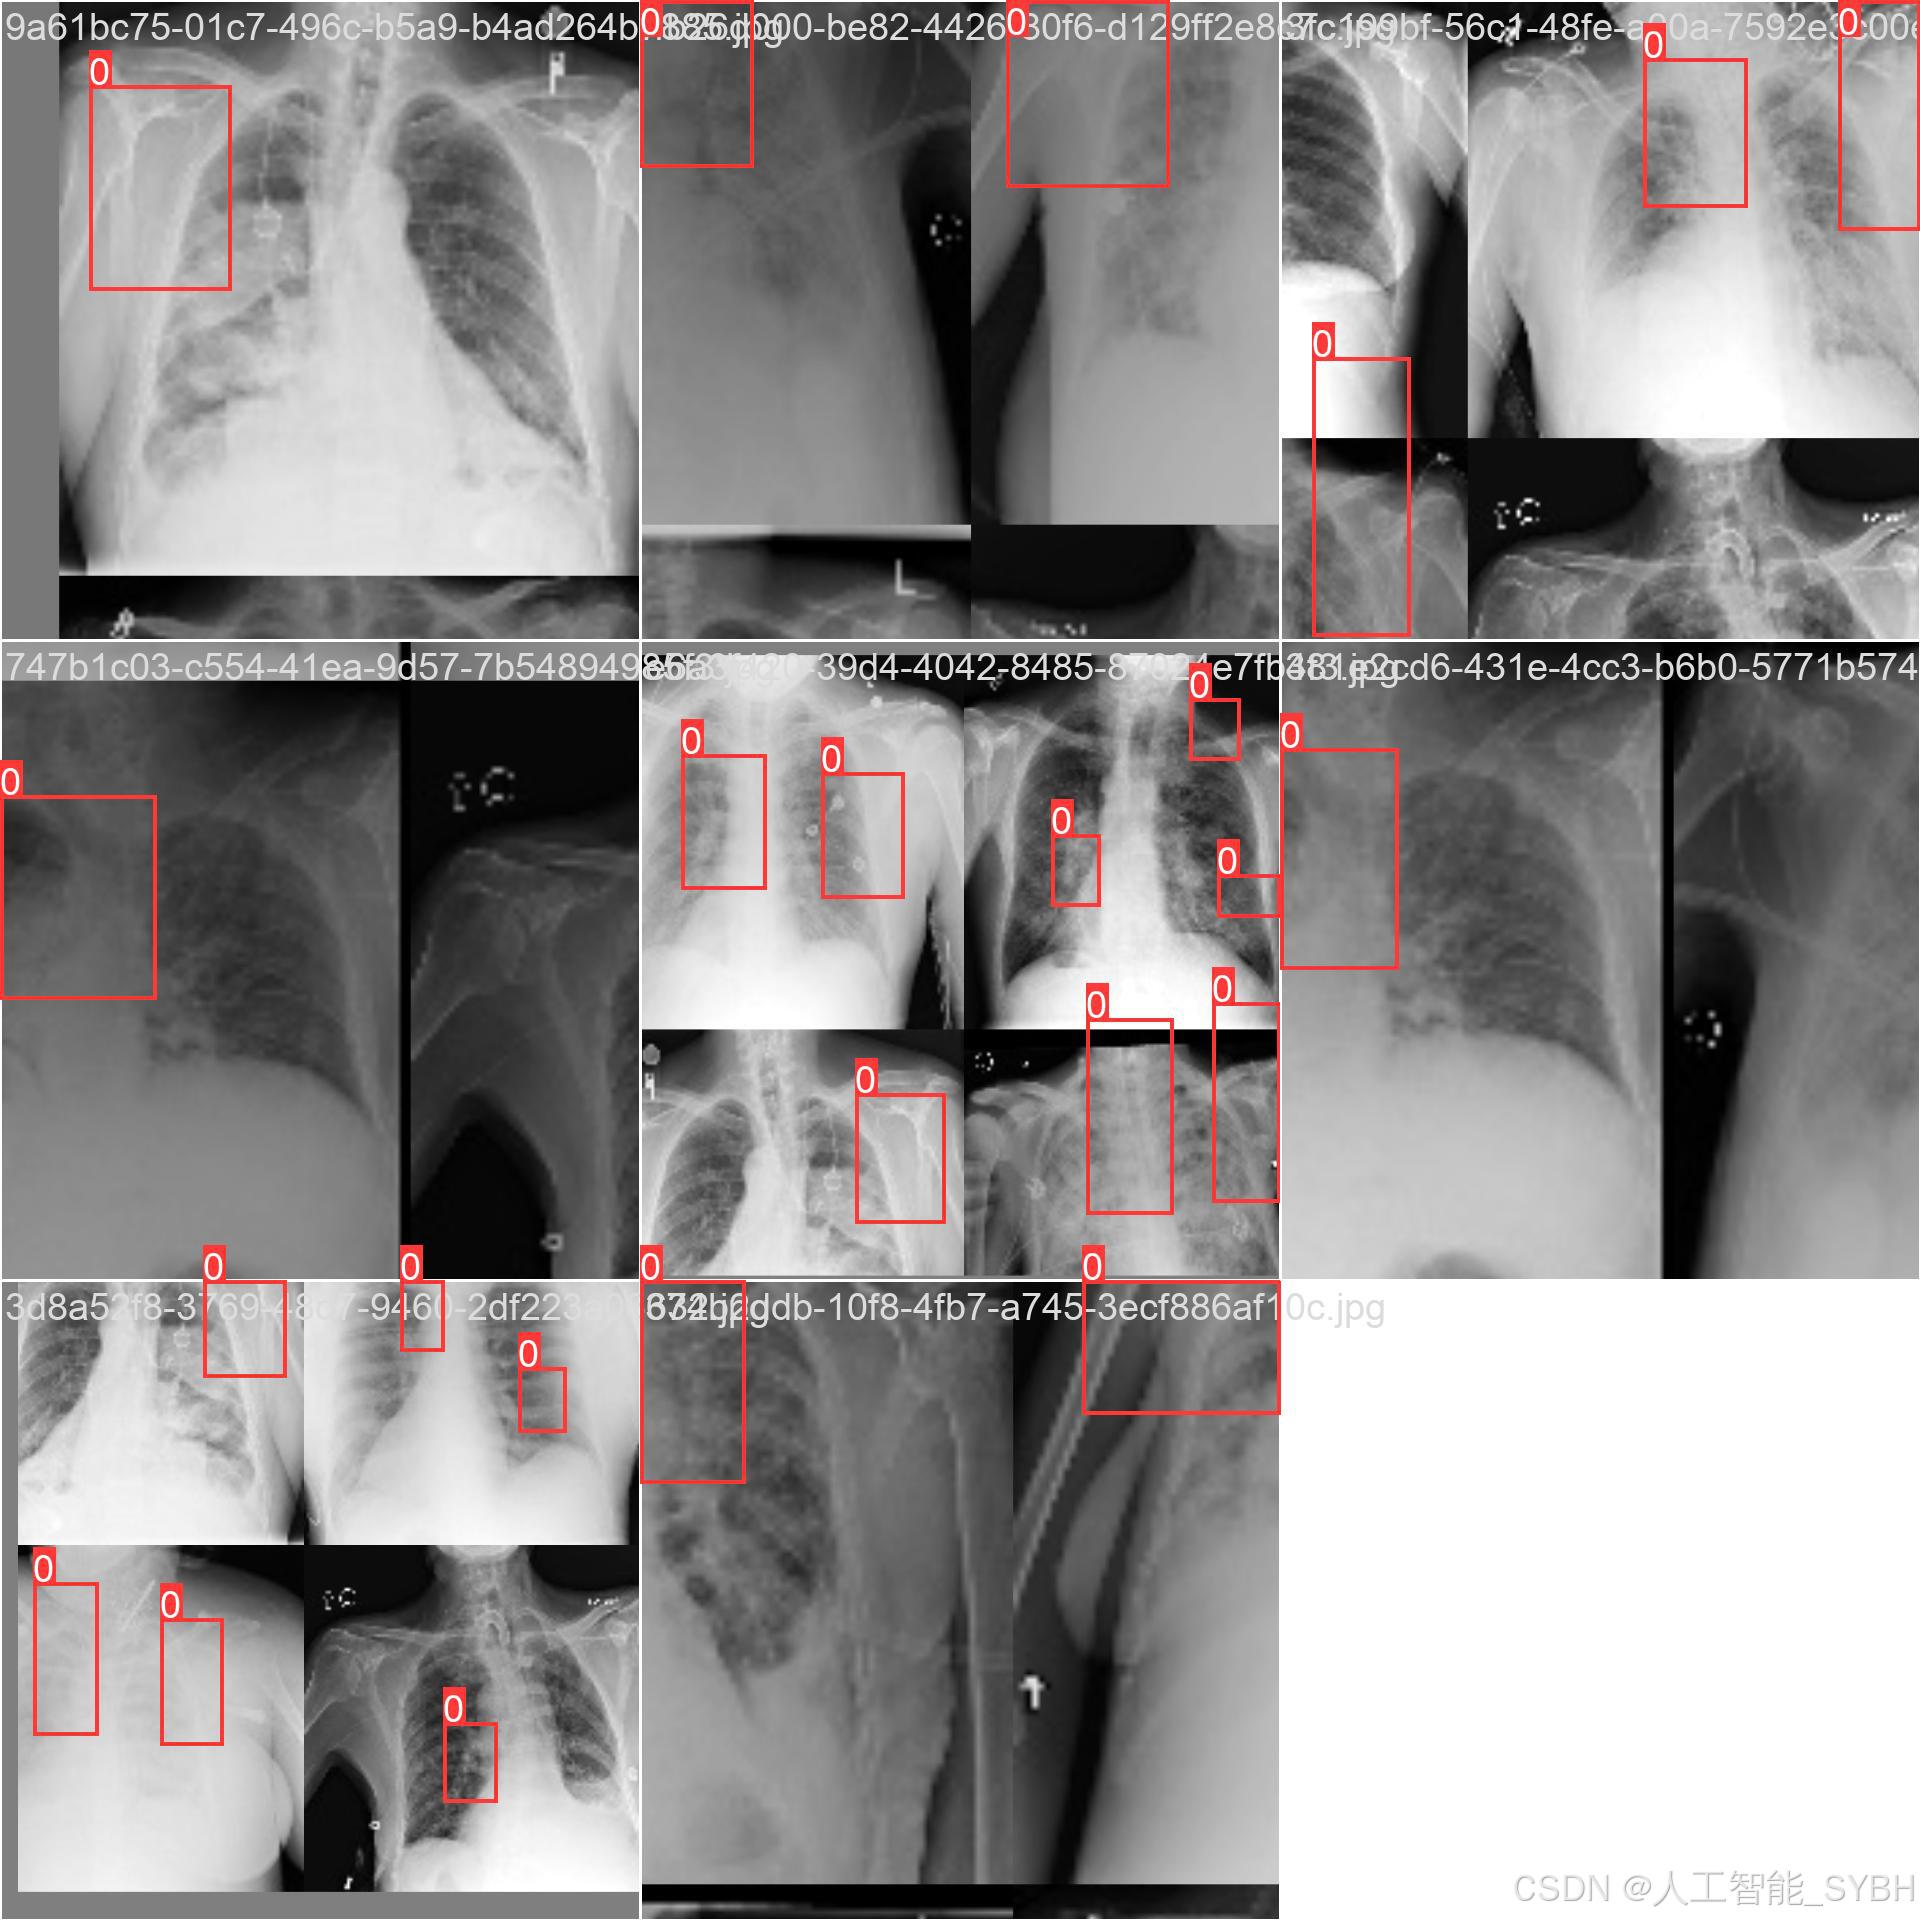

数据集名称: 肺炎检测数据集

数据集内容:

类别数量 (nc): 1类

类别名称: ['Pneumonia']

Pneumonia: 肺炎

数据集规模:

训练集: 3772张图像

验证集: 539张图像

测试集: 1078张图像

数据来源:

数据集通过收集医院中的胸部X光片构建,涵盖了不同年龄段、性别和病情的患者,以确保模型的泛化能力。

数据标注:

每张图像中的肺炎区域均使用边界框(Bounding Box)标注,并标注对应的类别。

数据集特点:

多样性: 数据集包含不同患者的胸部X光片,覆盖了多种病情和拍摄条件。

高质量: 图像分辨率高,标注精确,适合深度学习模型的训练。